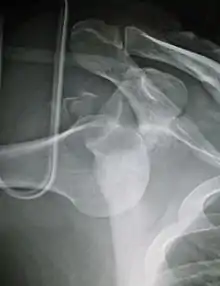

| Anterior dislocation of the left shoulder. | |

An anterior dislocation of the shoulder

Anterior dislocation of the right shoulder. AP X ray

Anterior dislocation of the right shoulder. Y view X ray.